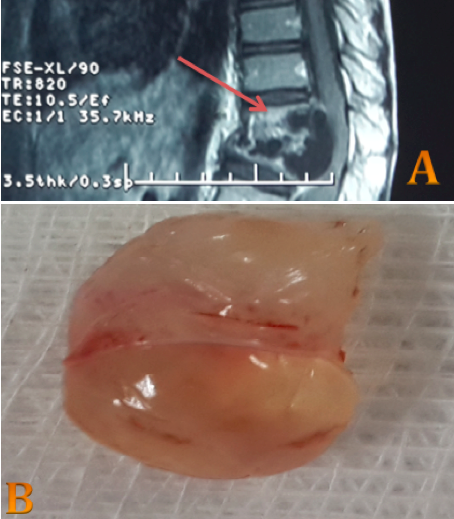

Une compression médullaire révélant une hydatidose vertébro-médullaire

La localisation vertébrale du kyste hydatique est de mauvais pronostic et reste exceptionnelle : 0,5 à 2,5% de l’ensemble des localisations hydatiques. Sa symptomatologie clinique est non spécifique avec une évolution lente mais inéluctable vers la compression médullaire ou radiculaire. Le diagnostic repose sur un faisceau d’arguments épidémiologiques, cliniques, biologiques et surtout radiologiques grâce aux moyens modernes d’imagerie. Le traitement reste essentiellement chirurgical, avec un pronostic défavorable et un taux de récidive pouvant atteindre les 40 %